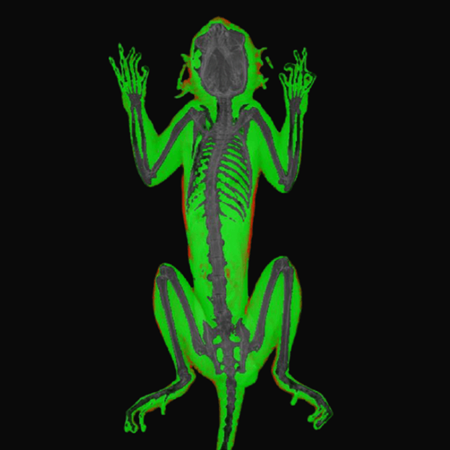

X-Ray Attenuation Image - Rat. Image Credit: Scintica Instrumentation Inc

Color Image - Rat. Image Credit: Scintica Instrumentation Inc

Bone Mineral Density Image - Rat. Image Credit: Scintica Instrumentation Inc